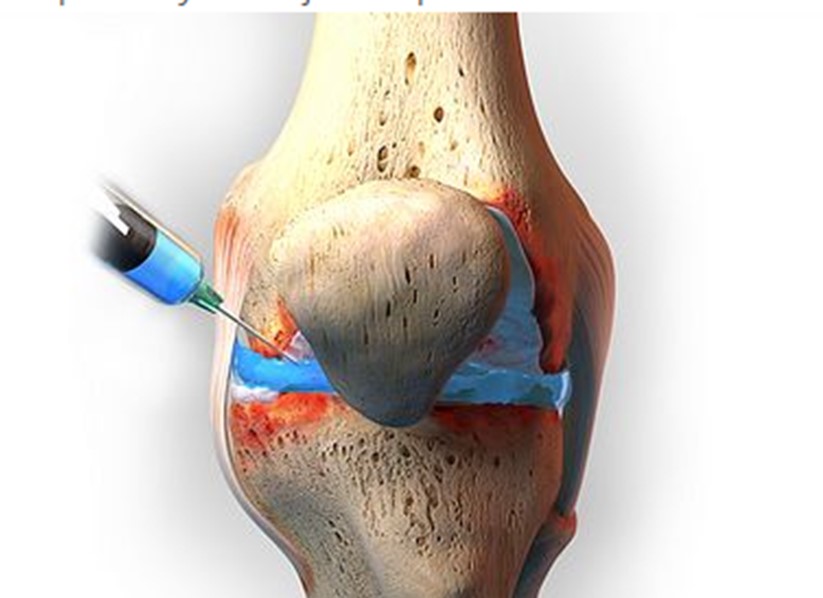

تزریق PRP: پلاسمای غنی از پلاکت به ناحیه آسیبدیده زانو تزریق میشود. این پلاسمای غنی از فاکتورهای رشد است که میتواند به التیام بافتهای آسیبدیده کمک کند.

در روش درمانی PRP زانو، یک نمونه از خون بیمار جمع آوری میشود و در دستگاه سانتریفیوژ قرار میگیرد. این فرآیند باعث جداشدن اجزاء مختلف خون، از جمله پلاسما، سلولهای قرمز و سفید و پلاکتها از یکدیگر میشود. به دلیل اینکه پلاکتها حاوی عوامل رشدی هستند که به التیام آسیبهای عروق خونی کمک میکنند، انتقال پلاکتهای غلیظ شده به ناحیه مورد نیاز از بدن، مانند زانو، میتواند به فرایند التیام طبیعی بدن کمک کرده و آن را تسریع کند.

سپس، پزشک زانوی شما را بیحس میکند و PRP را وارد فضای مفصل زانو تزریق میکند. در برخی موارد، از سیستم اولتراسوند برای راهنمایی تزریق استفاده میشود.